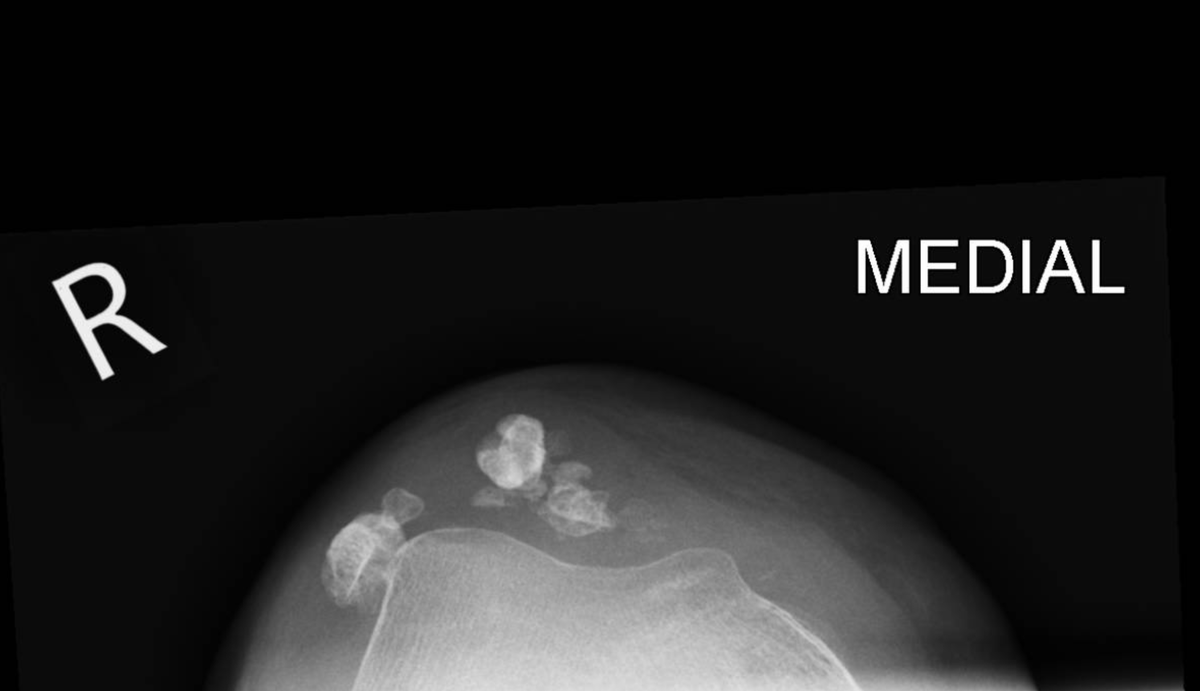

I've put the skyline view x-ray of her knee in too coz it's cool

Always check the images yourself - and bear in mind can pick up helpful pathology on non-dedicated series so worth scrutinising it all